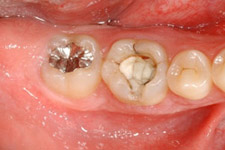

移植後4ヶ月。

移植歯はコンポジットレジンで修復が行われています。